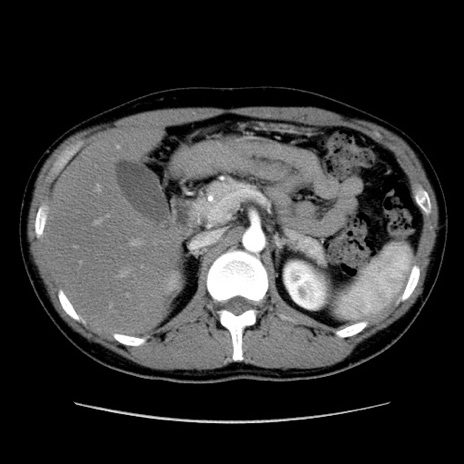

症例36(横断像)

【症例】20歳代 男性

【主訴】心窩部痛

【現病歴】今朝より上腹部痛あり。一旦軽快していたが再度出現したため救急要請。昨日夕に白身の魚を含む刺身を食べた。

【身体所見】BP 136/89mmHg、HR 74/min、BT 37.0℃、腹部:膨満、軟、心窩部に圧痛あり。反跳痛なし、筋性防御なし、腸雑音やや亢進あり。

【データ】WBC 17700、CRP 0.48